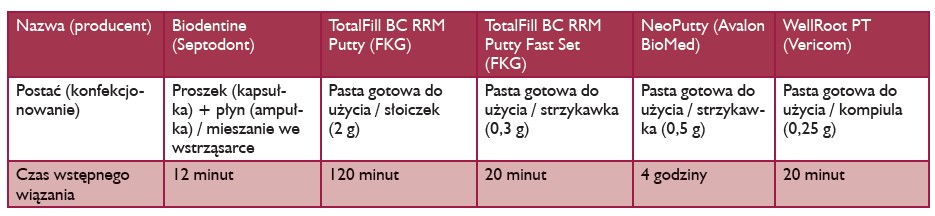

W tabeli I umieszczono również czasy wiązania nowych materiałów bioceramicznych. Są one stosunkowo krótkie, co wymusza na operatorze dość szybką pracę. Odrębny problem stanowi wypłukiwalność materiału. Ta cecha nie jest istotna pod warunkiem, że nie wykonuje się płukania kanału (części środkowej i koronowej) na wizycie, podczas której założono cement. O ile materiały w postaci gotowej pasty po wstępnym związaniu, tj. po około 20 minutach, są dość odporne na wypłukiwanie, to preparat Biodentine, który również wiąże dość szybko nie powinien być po 12 minutach od założenia, tj. po wstępnym związaniu, poddawany działaniu roztworów płuczących.

TABELA I. Preparaty bioceramiczne uzyskiwane w wyniku syntezy stosowane do zamknięcia otworu wierzchołkowego podczas apeksyfi kacji jednowizytowej